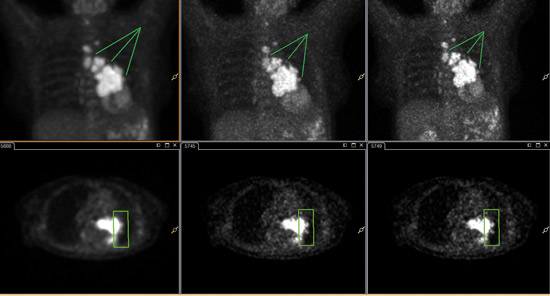

Images reconstructed with ×Fine for this lung cancer patient demonstrate enhanced lesion detectability.

Images courtesy of University Hospital Salzburg, Austria

×Fine and ×Sharp further contribute to image quality, seen here in enhanced resolution. ×Fine reconstruction (center) and ×Fine with ×Sharp reconstruction (far right).